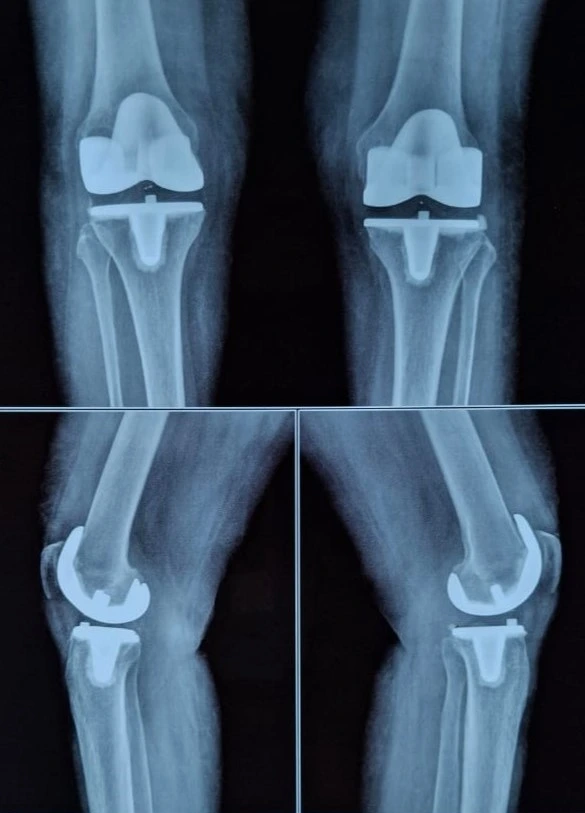

Quality and affordable healthcare has long been the essence in the field of medical sciences & treatment. Every patient expects an early diagnosis and a planned approach to treatment procedures with affordability and access to quality healthcare. Knee replacement, Hip replacement, Fracture treatment are being done by Dr.P.Sankaralingam at very affordable costs without compromising on quality.

Dr.P.Sankaralingam M.S(ortho)., DNB (ortho).,MNAMS is an experienced senior consultant Orthopaedic surgeon who does about 350 joint replacement surgeries per year in addition to treatment of Trauma cases.

• Hip & Knee Replacement and Revision Surgeries

Accomplishment